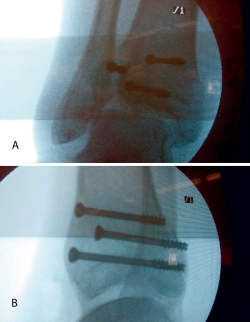

A raíz del artículo de Caspari(11), comenzamos a utilizar la artroscopia en nuestro medio en las fracturas de meseta tibial Schatzker de tipo II, en las que realizábamos la elevación del fragmento hundido mediante el uso de impactores desde la zona diafisometafisaria de la tibia, relleno del defecto con cemento biocompatible y fijación con tornillos canulados con arandela. Publicamos nuestra experiencia en los Cuadernos de Artroscopia en 1998(12)(Figuras 2 y 3).

Figura 2. Técnica quirúrgica en fracturas de meseta tibial asistidas por artroscopia: elevación del fragmento hundido mediante impactor.

Figura 3. Técnica quirúrgica en fracturas de meseta tibial asistidas por artroscopia: relleno con cemento biocompatible y fijación con tornillos canulados de esponjosa.